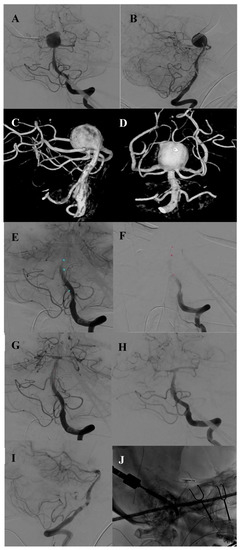

| 2 | 44 | Male | Partially thrombosed distal left side dissecting basilar artery aneurysm with secondary wall hematoma Ampullary exit of the left double-laid SCA from the aneurysm fundus | 11 × 8 × 8 | no | Thunderclap headache | N/A | N/A | 15 | 0 | 5 |

| 2 | 10 | 2 | Small remnant at the neck to preserve the SCA exit No aneurysm perfusion All branches open | ASCENT® 4 × 7 balloon (DePuy Synthes) | None |